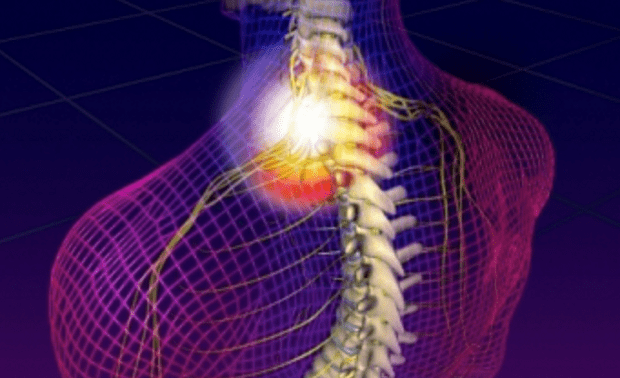

Egy rossz mozdulat, egy kényelmetlen alvó-pozíció elegendő ahhoz, hogy szúró, égő fájdalomban legyen részünk a nyakunkban, a vállunkban, a hátunkban vagy a karunkban egy becsípődött ideg miatt. Szerencsére ez a kellemetlen állapot elkerülhető, és ha már kialakult, jól kezelhető.